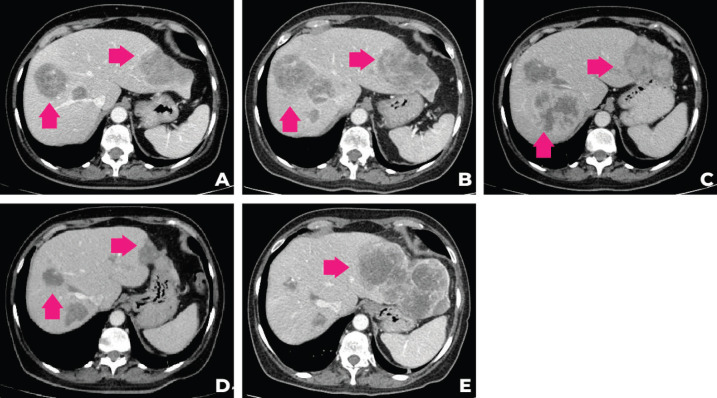

考慮到患者的臨床病程和多基因檢測包的結(jié)果,MTB 第二次會議討論建議進(jìn)行腫瘤靶向藥物基因檢測850的遺傳咨詢,并開始使用他拉唑帕尼進(jìn)行全身治療。 遺傳咨詢后,進(jìn)行了 33 個基因組,包括與結(jié)腸癌、婦科癌和結(jié)直腸癌相關(guān)的基因(APC、ATM、AXIN2、BARD1、BMPR1A、BRCA1、BRCA2、BRIP1、 CDH1、CHEK2、DICER1、EPCAM、GREM1、MLH1、MSH2、MSH3、MSH6、MUTYH、NBN、NF1、NTHL1、PALB2、PMS2、POLD1、POLE、PTEN、RAD50、RAD51C、RAD51D、SMAD4、SMARCA4、STK11、TP53)的基因檢測。在所有檢測的基因中沒有任何一個被發(fā)現(xiàn)任何相關(guān)的突變或變異。 2021 年 9 月,經(jīng)過 talazoparib 治療 3 個月后,觀察到腹痛和肝臟部分反應(yīng)的臨床改善。 在提交本病例時(2021 年 12 月),腫瘤反應(yīng)正在進(jìn)行中。 圖 2 描繪了患者主要放射學(xué)發(fā)現(xiàn)的總結(jié),圖 3 描繪了患者演變的時間表。

圖 2:患者計(jì)算機(jī)斷層掃描在不同時間段的演變。 (a):2020 年 12 月的 CT,(b):2021 年 4 月,(c):2021 年 6 月,(d):2021 年 9 月,(e):2021 年 12 月